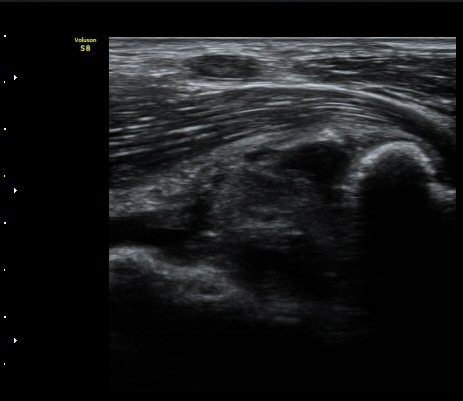

ÃÊÀ½ÆÄ °Ë»ç